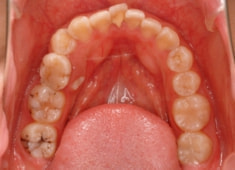

治療後(1年12ヶ月後)